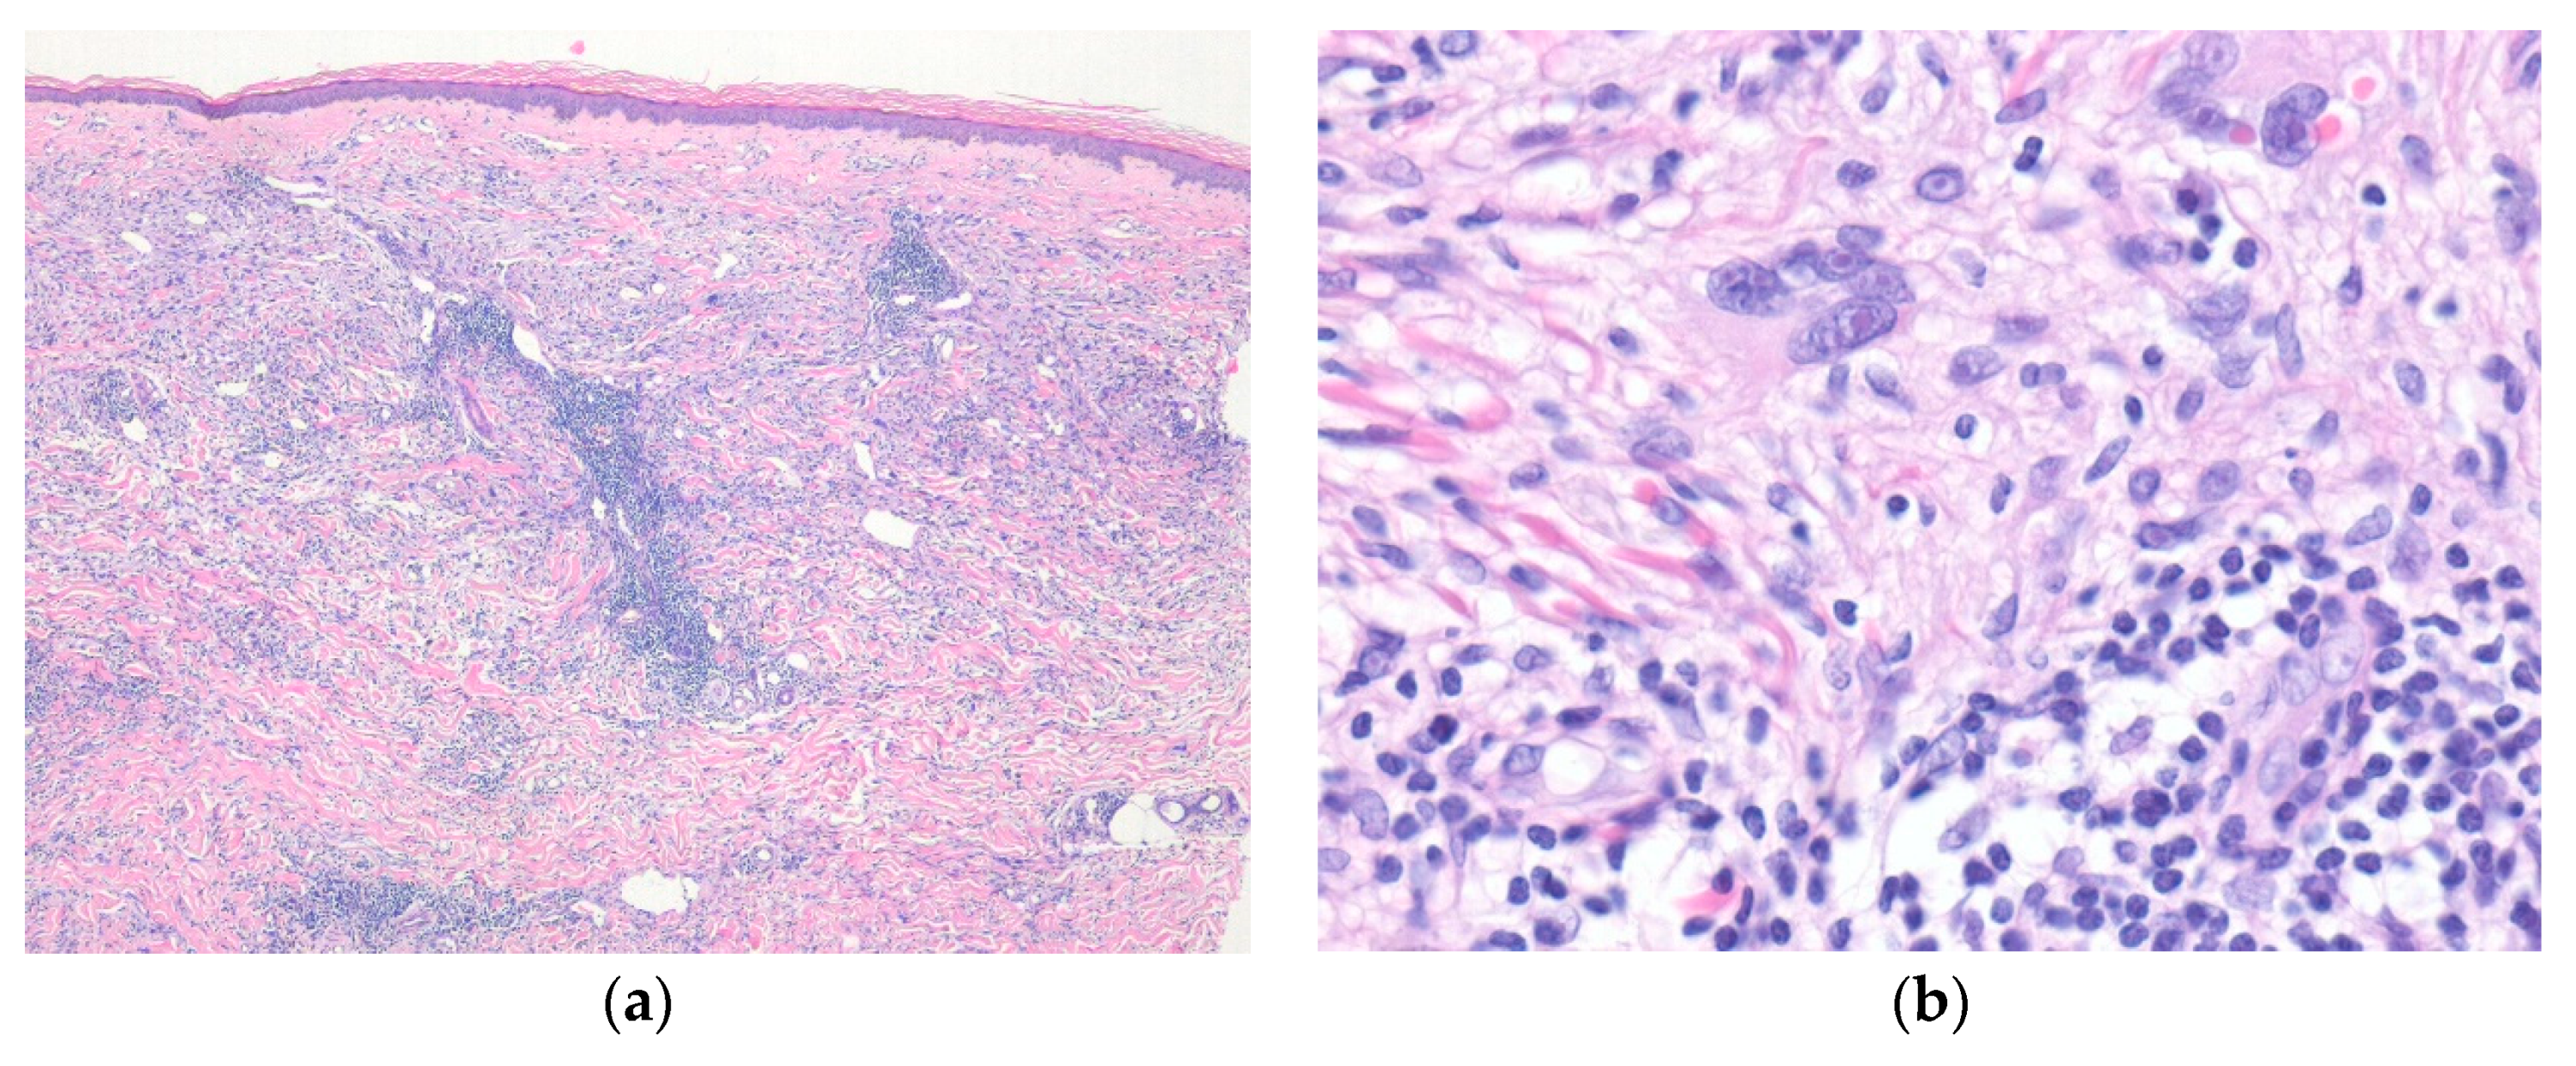

4. Epithelioid Smooth Muscle, Perivascular, and Vascular Tumors

4.1. Cutaneous Smooth Muscle Tumors